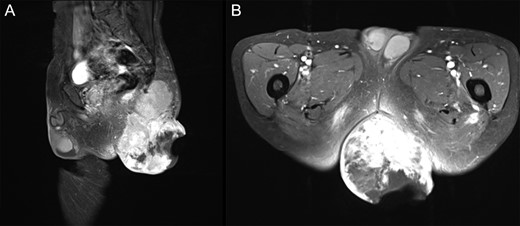

Two months after initial examination, the patient was hospitalized at our department. To prevent a secondary infection from defecation, we first performed an artificial anastomosis. Mohs’ paste was subsequently applied a total of 16 times over 3 months. The wound infection improved 2 weeks after administering Mohs’ paste and antibiotics (ampicillin/sulbactam). After the infection subsided, three courses of neoadjuvant chemotherapy (Doxorubicin) were performed. The disintegrated portion of the tumor recessed by using Mohs’ paste, and the bleeding, exudation and odor subsided. Moreover, the patient was able to tolerate both sitting and supine positions (Fig. 1B). The contrast-enhanced MRI revealed that the protruding area of the tumor was resected with no increase in the internal tumor size (Fig. 3A and B). One day prior to curative surgery, embolization of the left inferior gluteal artery.

Pre-operative T1WI contrast-enhanced MRI with fat suppression. (A) Sagittal image. (B) Axial image. The protruding tumor was resected, and the internal tumors showed no considerable changes in size.